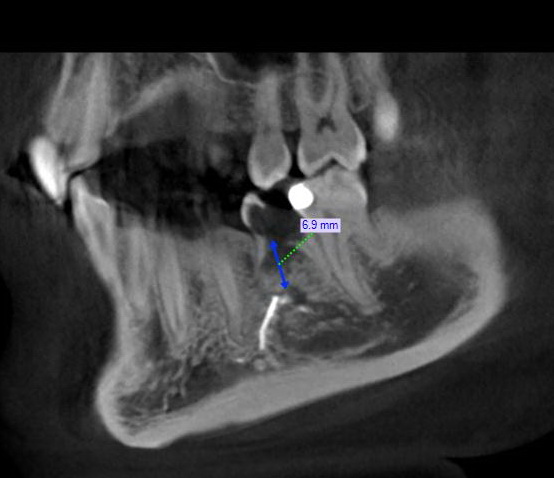

Может БОИ это как раз мой случай?

Напоминаю, Ваши же рисунки на моих снимках (инородное тело в кости):

кстати да. вполне может быть. если они уложатся в эти 6,9 мм.

Ваш случай называется "мечта имплантолога"

Инородное тело - пломбировочный материал - имплантат проходит сквозь него без ущерба для остеоинтеграции.

До нижнечелюстного канала как до луны.

Ставьте обычный винтовой и не партесь.

Работа не вечная, и если БОИ дезинтегрируется - то в кости будет хуже, чем от врыва гранаты.

там петля нижнечелюстного канала (очень нестандартная) + остеосклероз = понижена васкуляризация.

Да - петля, возможно.

Но и в 6.9 можно вложится винтовым без заморочек.

Косточка по ширине нормальная, а остеосклероз здесь - это кортикалка челюсти.

Будет бикортикальная фиксация...)))